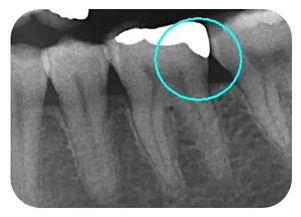

嵌體位于牙體內(nèi)部,只能修復(fù)缺損的牙體組織,不能保護剩余的牙體組織。

嵌體在咬合受力后會將力傳導(dǎo)至洞的側(cè)壁,在剩余牙體內(nèi)產(chǎn)生拉應(yīng)力,過大的拉引力會造成牙體折裂。 要避免咬硬物,注意勿進食過硬食物,以免因給牙齒帶來過大的負(fù)荷而影響嵌體的長期使用。

嵌體位于牙體內(nèi)部,只能修復(fù)缺損的牙體組織,不能保護剩余的牙體組織。嵌體在咬合受力后會將力傳導(dǎo)至洞的側(cè)壁,在剩余牙體內(nèi)產(chǎn)生拉應(yīng)力,過大的拉引力會造成牙體折裂。